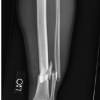

Osteoporosis is a generalized condition, not restricted to a localized area or single bone. This means that a fragility fracture is only a partial manifestation of the underlying pathological process. Thus, stabilization of the fragility fracture only addresses the single region of fractured and does not address the other bones. This still leaves the patient with an increased risk of fracture in the opposite femur, vertebra, and other bones. Studies have also shown that an individual who sustains a fragility fracture has a substantial increase in the likelihood to sustain another fracture [2]. This demonstrates the need for treatment of the osteoporosis. Another problem is osteoporosis very often remains undiagnosed [3]. Despite osteoporosis being easy to suspect in patients with fragility fractures by the advanced age of the patients, the presence of osteolysis on radiographs, classical locations of fragility fractures, and thin cortical bone encountered intraoperatively, patients are rarely evaluated for osteoporosis. This lack of evaluation is the leading cause for osteoporosis going untreated [4].

Evaluation requires estimation of serum calcium, serum Vitamin D levels, and dual-energy X-ray absorptiometry (DEXA) scan. DEXA scan is not available in smaller centers and is more expensive than routine radiographs. Another reason given by many is that treatment of osteoporosis is expensive and hence, patients are not willing to pay for prophylactic treatment of a condition. However, these are not valid reasons to justify the lack of diagnosis and treatment. Estimation of serum calcium and Vitamin D are simple, inexpensive, and available routinely. The supplementation of calcium and Vitamin D are inexpensive and play a major role in the treatment of osteoporosis. DEXA scans are now available in an increasing number of centers and are now less expensive than CT scans. The price of a DEXA scan in most centers today is <Rs.1800. If the diagnosis of osteoporosis is doubtful and DEXA scan not possible, at least a diagnosis of osteopenia can be made on radiographs. Osteopenia coupled with a fragility fracture would necessitate treatment in most cases. Singh’s index is a grading of the osteopenia of the proximal femur which can be made on radiographs alone.